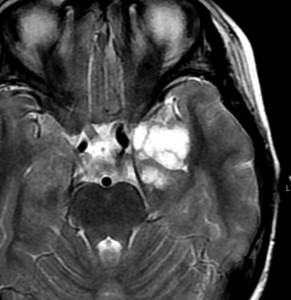

その2年後の画像です。右小脳半球に再発しています。右側頭葉腫瘍との連続性は全くありませんでした。脳幹部にも腫瘍はありません。遠隔再発 remote recurrenceというもので,星細胞系腫瘍 astroytic tumor AAやGBMではよく知られている現象です。乏突起膠細胞系腫瘍でもまれにみられます。